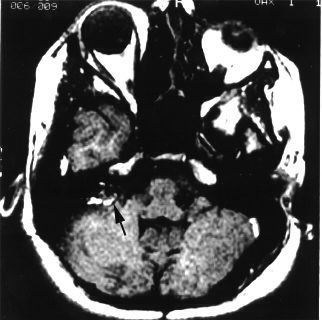

Badania profilaktyczne pacjentów z grup ryzyka - to jedna z propozycji rozpoczętego w Poznaniu Europejskiego Tygodnia Profilaktyki Nowotworów Głowy i Szyi. Według danych nowotwory te zajmują szóste miejsce na świecie pod względem zachorowalności.